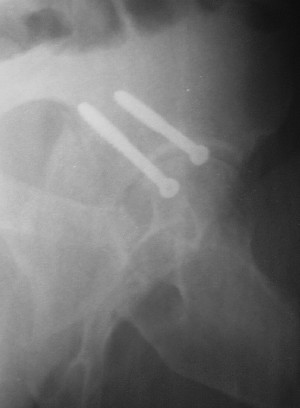

Послеоперационный снимок прямой 5/05/03

Послеоперационный снимок боковой 5/06/03

Больной 18 мая 2003 года в автоаварии получил перелом левой вертлужной впадины, вывих бедра. Госпитализирован в один из стационаров области.Вывих вправлен. В последствии бедро вывихивалось еще дважды. На консультацию был представлен снимок от 19.05.03г., больной переведен к нам 3.06.03г. Снимок при поступлении - перелом впадины, задне-верхний вывих бедра. 05.06.2003 г. выполнено открытое вправление вывиха левого бедра и остеосинтез стенки вертлужной впадины двумя винтами. Послеоперационный период без осложнений. Объем движений в левом тазобедренном суставе восстановился полностью. Выписан на амбулаторное лечение в удовлетворительном состоянии с рекомендациями 3 месяца ходить на костылях без нагрузки на оперированную конечность. На контрольных рентгенограммах левого тазобедренного сустава 13.10.2003 г. - признаки консолидации перелома; плотность, форма головки и состояние суставных поверхностей удовлетворительные. Разрешена дозированная осевая нагрузка, на конечность с использованием дополнительной опоры. 19.12.2003 г. больной обратился с жалобами на боли в левом тазобедренном суставе. На рентгенограммах левого тазобедренного сустава 19.12.2003 г., 20.02.04г. - асептичекий некроз головки бедра. 5.04.04г. - эндопротез. Сейчас ходит без трости, не хромает. Особенность эндопротезирования - при удалении винтов прослежена линия перелома заднего края впадины и предложено установить чашку несколько меньшего диаметра, чтобы она была покрыта несломанной частью.